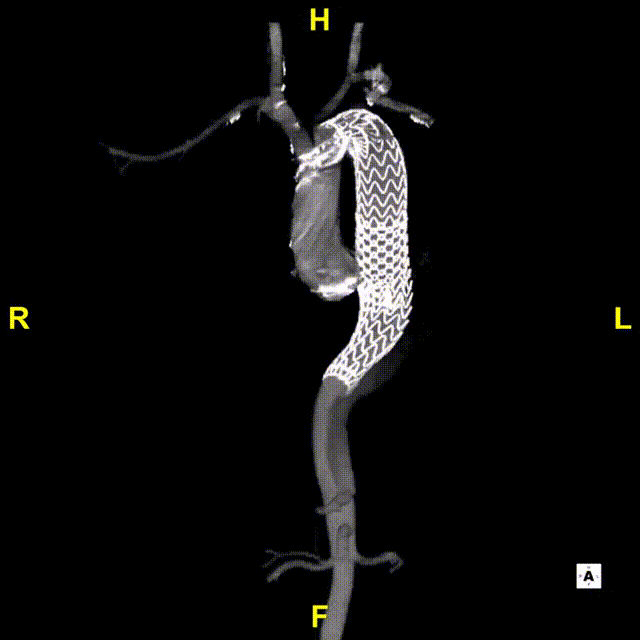

术后随访

术后随访复查造影可见胸主动脉显影良好,假腔血栓化,支架近端无“鸟嘴”,支架内显影良好无内漏。

gore医疗怎么样「胸有乾坤」可调可控 精准出击——四川大学华西医院肖正华教授团队:CADS治疗B型主动脉夹层病例分享_https://www.jmylbn.com_新闻资讯_第29张

术后CTA

gore医疗怎么样「胸有乾坤」可调可控 精准出击——四川大学华西医院肖正华教授团队:CADS治疗B型主动脉夹层病例分享_https://www.jmylbn.com_新闻资讯_第30张

术后三维重建

gore医疗怎么样「胸有乾坤」可调可控 精准出击——四川大学华西医院肖正华教授团队:CADS治疗B型主动脉夹层病例分享_https://www.jmylbn.com_新闻资讯_第31张

术后三维黑白重建